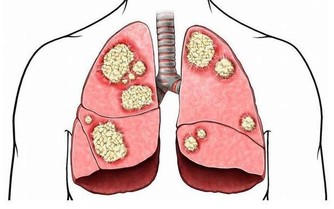

1. 癌症只是一種疾病

實際上,目前我們已經發現了數百種癌症,每個都具有獨特的分子特徵和可變的臨床表達。比如,在神經腫瘤學中,已經確定了至少120種腦和脊髓癌亞型。對於這種多樣化的敵人,我們的診斷和治療方法必須擴大,也必然很難。